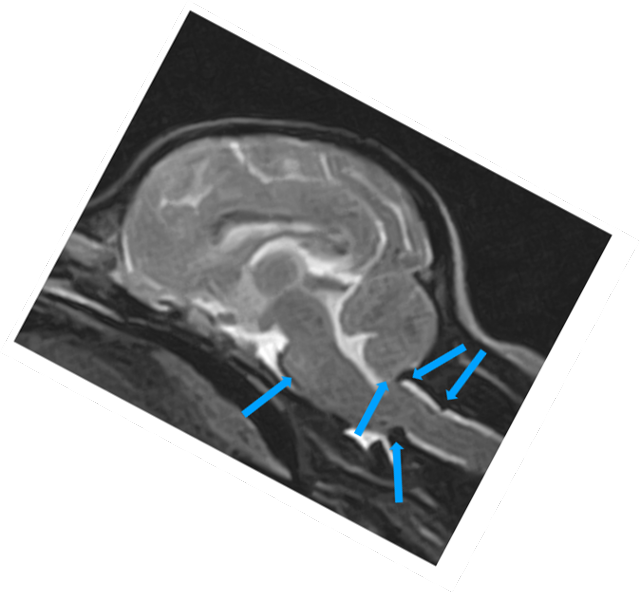

W obrębie mózgowia i trzewioczaszki najczęstszymi wskazaniami do badania MRI są:

• proces nowotworowy

• wodogłowie

• ziarniakowe zapaleniu mózgu i opon mózgowych

• diagnostyka zmian udarowych

• wstępna diagnostyka tętniaków i malformacji naczyniowych

• malformacje Chiariego

• wady złącza czaszkowo mózgowego